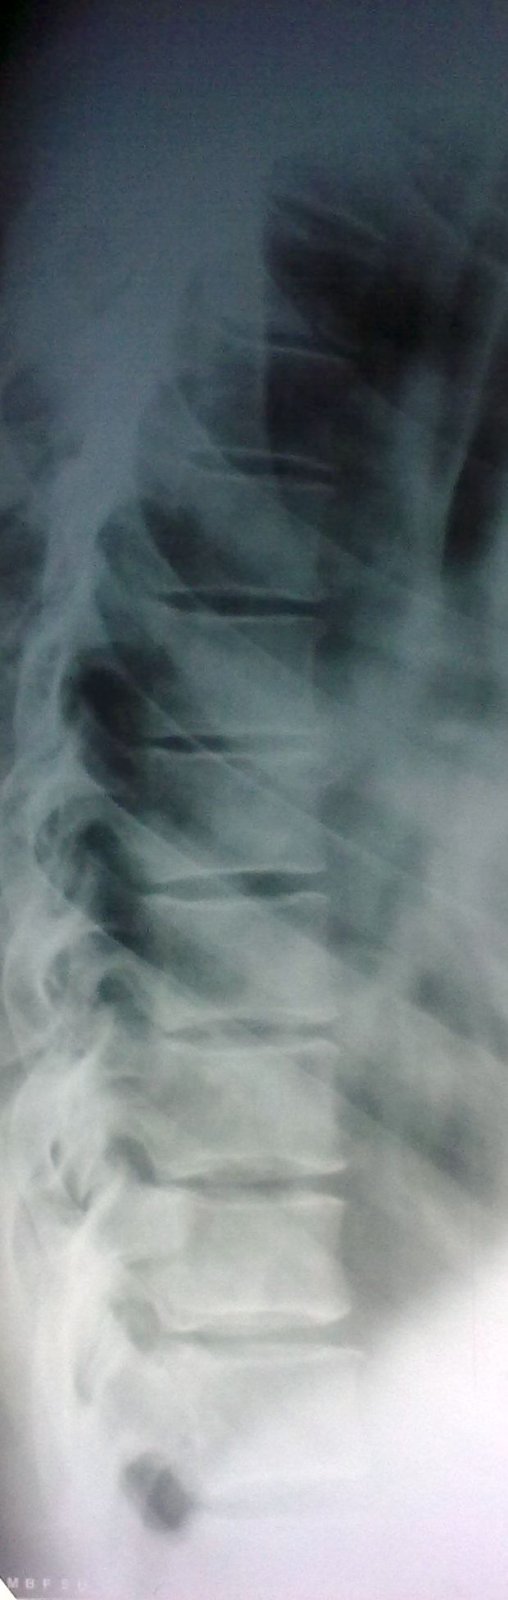

Оказываетя, что за год до этого пациенту была удалена опухоль на бедре, гистологически синовиальная саркома. Было произведено КТ ОГК. Подтвердили пневмонию, мета в позвоночник.

Для полной картины я сделал рутинную рентгенограмму позвоночника. Можно с большим натягом придраться к одному из тел (TH3), имея КТ. Прямая не информативна. А вопрос такой: могут ли быть эти изменения в легких отголоском той операции.

Придраться к телу позвонка можно.

Но, вот после КТ можно, по всей видимости, придраться и к ребрам?